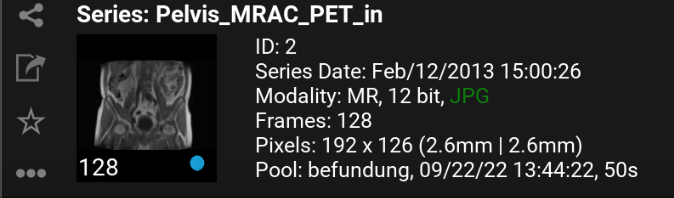

9.2.2. Serien Details

Mehr Details über eine Serie können Sie in der Serienauswahl einsehen.

Pool: Name des Datenpools; Zeitpunkt, wann die Serie in mRay verfügbar war; Transferzeit vom PACS zu mRay